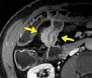

Souhrn: Úvod: Zobrazovací metody mají v diagnostice pacientů s Crohnovou chorobou nezastupitelnou úlohu. V současné době existuje několik skórovacích systémů, jejichž cílem je pomocí předem stanovených parametrů objektivizovat hodnocení zánětlivého postižení střeva. Cílem této práce bylo srovnání nálezu zánětlivého střevního postižení na koloskopii a magnetické rezonanci (MR) při použití skórovacího systému MaRIA. Materiály a metody: Pacienti s Crohnovou chorobou podstoupili v rozmezí do 2 měsíců koloskopii a MR enterografii ve Fakultní nemocnici Brno v letech 2020–2022. Aktivita onemocnění na koloskopii byla hodnocena pomocí SES-CD a Rutgeerts score, na MR pomocí MaRIA skóre (zesílení stěny, její sycení, edém a přítomnost ulcerací). Nálezy z obou zobrazovacích metod byly srovnány, koloskopie byla zvolena zlatým standardem. U každého pacienta bylo analyzováno terminální ileum, tlusté střevo (rozdělené anatomicky na čtyři segmenty) a rektum. Výsledky: V této retrospektivní studii bylo analyzováno 203 střevních segmentů u 43 po sobě jdoucích pacientů (42 % mužů). Senzitivita MR enterografie v hodnocení aktivity střevního zánětu byla 62 %, specificita 94 %. Všechny parametry určující aktivitu zánětu na MR byly signifikantně vyšší u pacientů s aktivitou dle koloskopie a celková hodnota MaRIA skóre byla rovněž vyšší v této skupině (12,76 ± 7,48 vs. 5,27 ± 3,45; p < 0,001). Senzitivita se zvýšila na 90 % při izolované analýze tenkého střeva, při analýze tlustého střeva se naopak snížila na 34 %. Závěr: V naší studii jsme prokázali shodu mezi MR s použitím MaRIA skórovacího systému a koloskopií při hodnocení střevního zánětu u pacientů s Crohnovou chorobou. Klí ová slova: magnetická rezonance – koloskopie – Crohnova choroba – MaRIA

Hodnocení střevního postižení u pacientů s Crohnovou chorobou pomocí MaRIA skórovacího systému

203 střevních segmentů vyšetřeno na MR a koloskopii (17 % tenké střevo, 73 % tlusté střevo, 10 % rektum)

MaRIA = (1,5 × šíře stěny [mm]) + (0,02 × RCE) + (5 × edém stěny) + (10 × ulcerace)

tenké + tlusté střevotenké střevotlusté střevorektum senzitivita 62 %senzitivita 90 %specificita 96 %specificita 89 % specificita 94 %PPV 93 %NPV 86 %NPV 94 %

Parametry na MR: šíře stěny edém stěny sycení stěny (RCE) ulcerace stěny